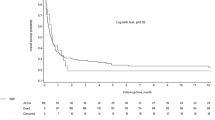

The mean SAPS II score (±SEM) during the first three postoperative days after the IO operation was significantly higher in TP patients (46.1 ± 3.7) compared to SP patients (29.7 ± 2.0) (p ≤ 0.001, T test). The time course of SAPS II values during the first three postoperative days after the initial operation is depicted in Fig. 9. SAPS II scores for TP patients on the first (47.1 ± 4.2), second (45.1 ± 4.0), and third postoperative days (44.9 ± 4.0) were significantly higher compared to SP patients on the respective days (30.7 ± 2.1, 28.4 ± 2.0, and 30.3 ± 2.5, respectively; p ≤ 0.001, p ≤ 0.001, and p = 0.004, respectively; T test; Fig. 9).

Time course of SAPS II scores in the postoperative period after the initial operation in patients who further developed tertiary peritonitis (TP) and patients who did not (SP). Mean SAPS II scores ± SEM values are indicated on the first three postoperative days (d1–d3). Significantly higher SAPS II scores for TP compared to SP during the whole period (p ≤ 0.001, p ≤ 0.001, and p = 0.004, respectively; T test).

The second parameter was the SAPS II score, initially designed to predict mortality and disease severity of critical ill patients.13,14 We could demonstrate that SAPS II was significantly higher during the first three postoperative days after initial operation in TP patients (46.0) compared to SP patients (29.7). Interestingly, the curves for TP and SP patients ran completely parallel to each other over the whole period. The receiver operator characteristic analysis on the second day revealed an area under the receiver operator characteristic curve of 0.797, which demonstrates the diagnostic potential of this scoring system for early identification of patients at risk for TP. Our results are consistent with a recent study that reported similar SAPS II scores for TP (45.6) and SP (31.9) patients—underlining the importance of this parameter.12